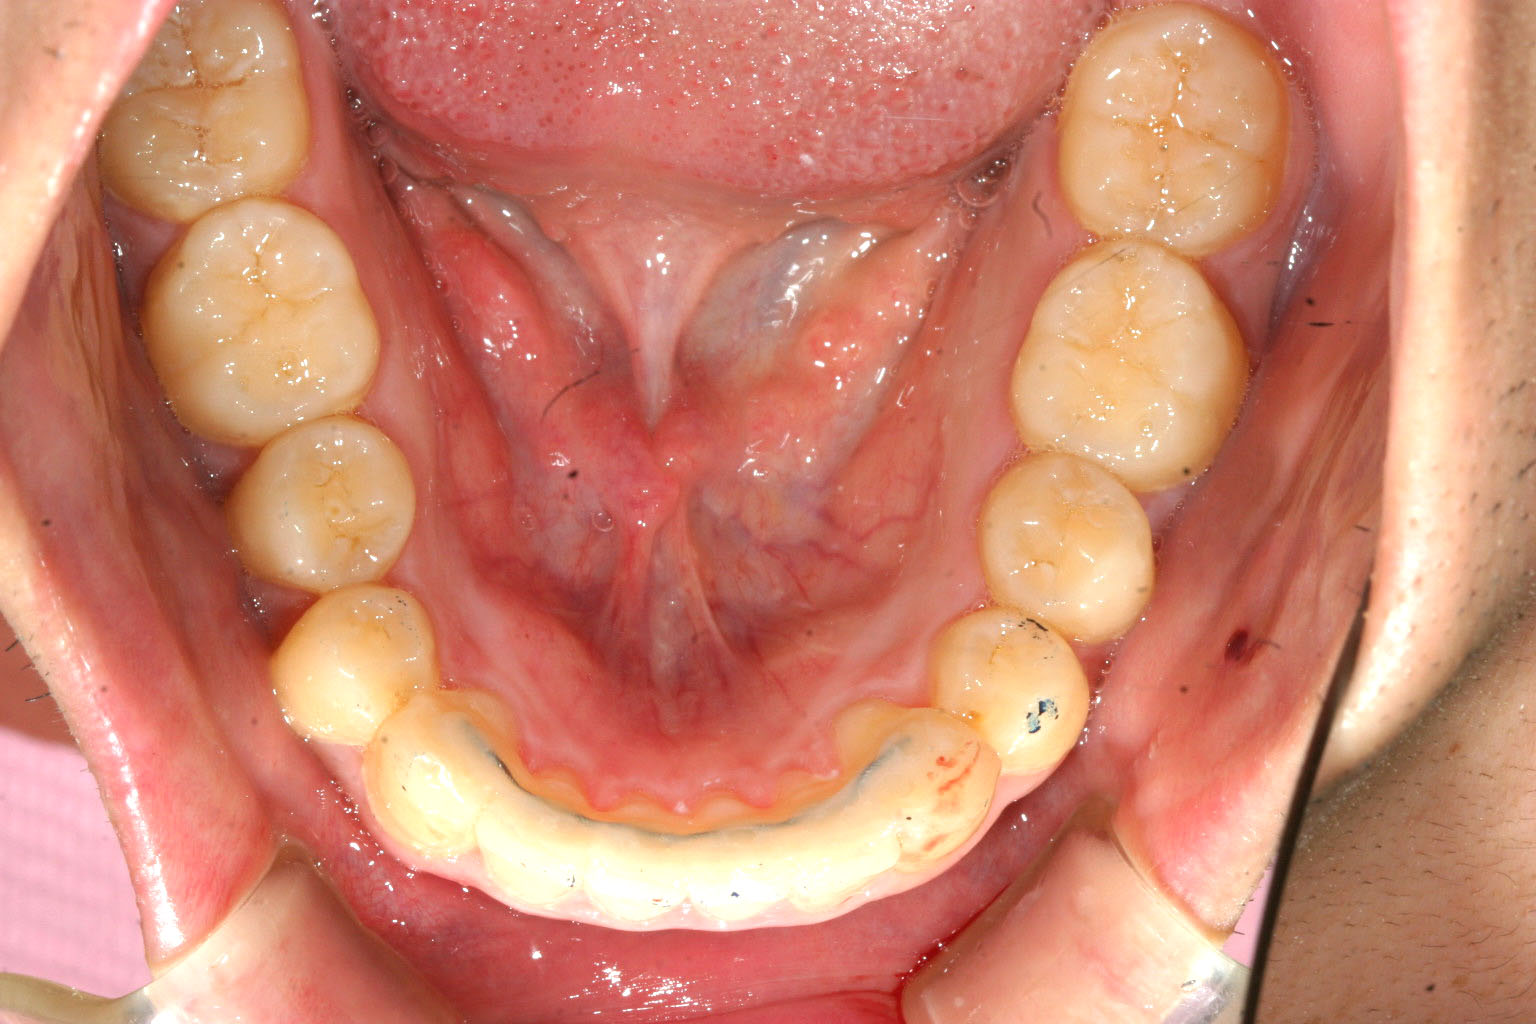

下顎も小臼歯部を広げました。

かなり入りました。

今回のケースは患者様の希望で抜歯せずに最大限に出っ歯を改善しました。

狭くなったアーチフォームの改善とインビザラインの得意技であるIPR(歯と歯の隙間を削る)を行う事によりここまで非抜歯でも改善できると言う症例です。